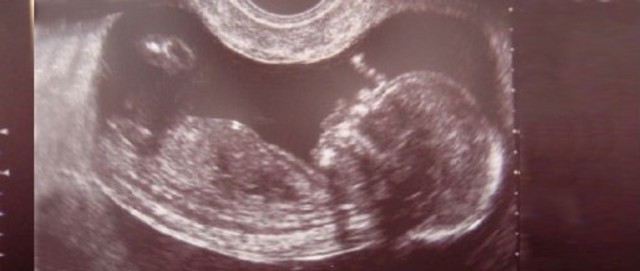

la cara tiene perfil humano, la barbilla ha crecido. Las orejas aún ocupan una posición baja y las uñas empiezan a crecer.

Los genitales tienen características femeninas y masculinas en función del sexo del nuevo ser aunque aún no se han formado por completo, por lo que todavía no es fácil aclarar el sexo.